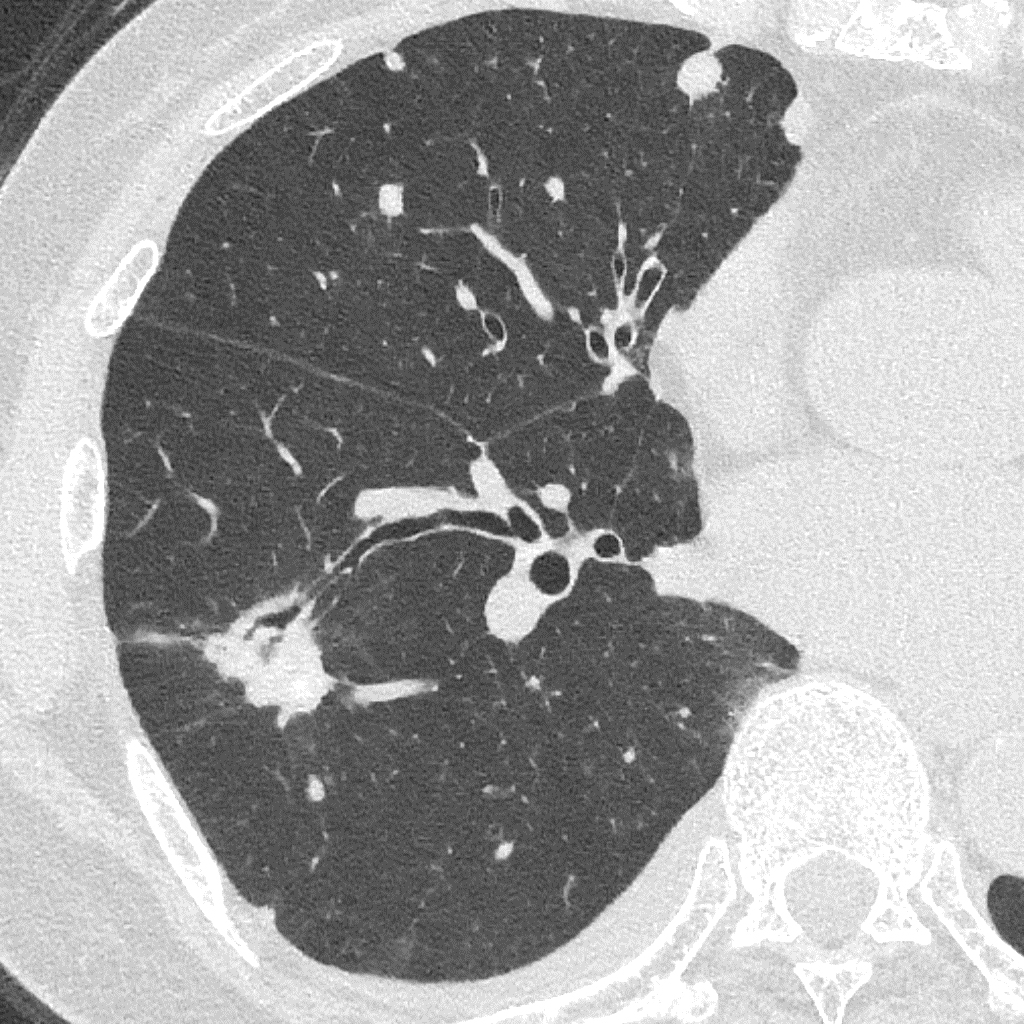

Порівняння звичайної роздільної здатності з ультрависокою роздільною здатністю (УРЗ)²

Звичайна КТ 0,5 мм

КТ з ультрависокою роздільною здатністю 0,25 мм ³